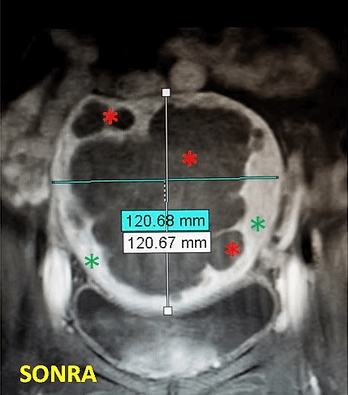

41 yaşında, kabızlık, gaz ve sık idrara çıkma şikayetleri var. Emar’da karını dolduran dev miyom (*) mevcut. Miyomektomi önerilmiş, ancak operasyonda rahimin alınabileceği söylenmiş. Embolizasyondan sonra dev miyomun ve bir başka küçük miyomun öldüğü ve küçüldüğü izleniyor. 7 ay sonra hasta şikayeti kalmamıştır.